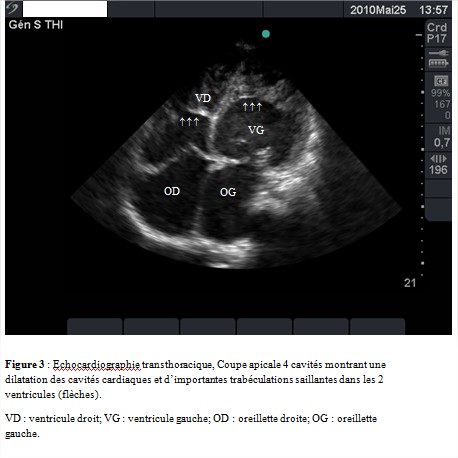

L’échocardiographie transthoracique concluait à une dilatation importante des cavités cardiaques (figure 3) (ventricule gauche en diastole = 74 mm; en systole = 67 mm; ventricule droit = 35 mm; surface de l’oreillette gauche = 34,7 cm²; surface de l’oreillette droite = 30 cm²), une hypocinésie globale des parois du ventricule gauche avec altération importante de la fonction systolique des deux ventricules (fraction d’éjection du ventricule gauche à 25 % et Tricuspid Annular Plane Systolic Excursion (TAPSE) à 7 mm). On notait la présence d’un contraste spontané intraventriculaire gauche. Le myocarde avait un aspect spongieux révélant la présence d`importantes trabéculations saillantes séparées par des cryptes localisées à l’apex et étendues à la paroi latérale du ventricule gauche (figure 3 et 4). La zone non compactée (ZNC) sous endocardique mesurait 5,5 mm contre 2,1 mm pour la zone compactée (ZC) sous épicardique (rapport ZNC/ZC = 2,61). Le Doppler couleur permettait de visualiser le remplissage intra-trabéculaire par le flux sanguin. Le ventricule droit était le siège d’importantes trabéculations saillantes séparées par des cryptes allant de l’apex à la partie moyenne de la cavité ventriculaire faisant évoquer une non-compaction du ventricule droit (figure 3 et 4). On notait également un remplissage intra-trabéculaire par le flux sanguin au Doppler couleur. Les valves étaient fines avec une insuffisance mitrale et tricuspide modérée par dilatation de l’anneau. Il existait une hypertension artérielle pulmonaire sévère avec une pression artérielle pulmonaire systolique mesurée à 69 mmHg.